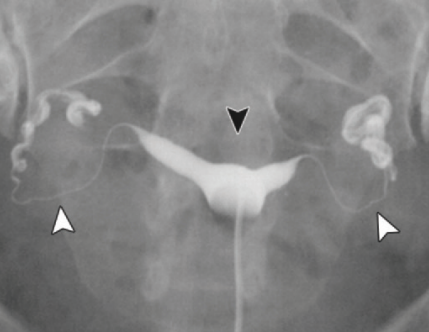

Utérus Didelphe

Bicorne VS Septé